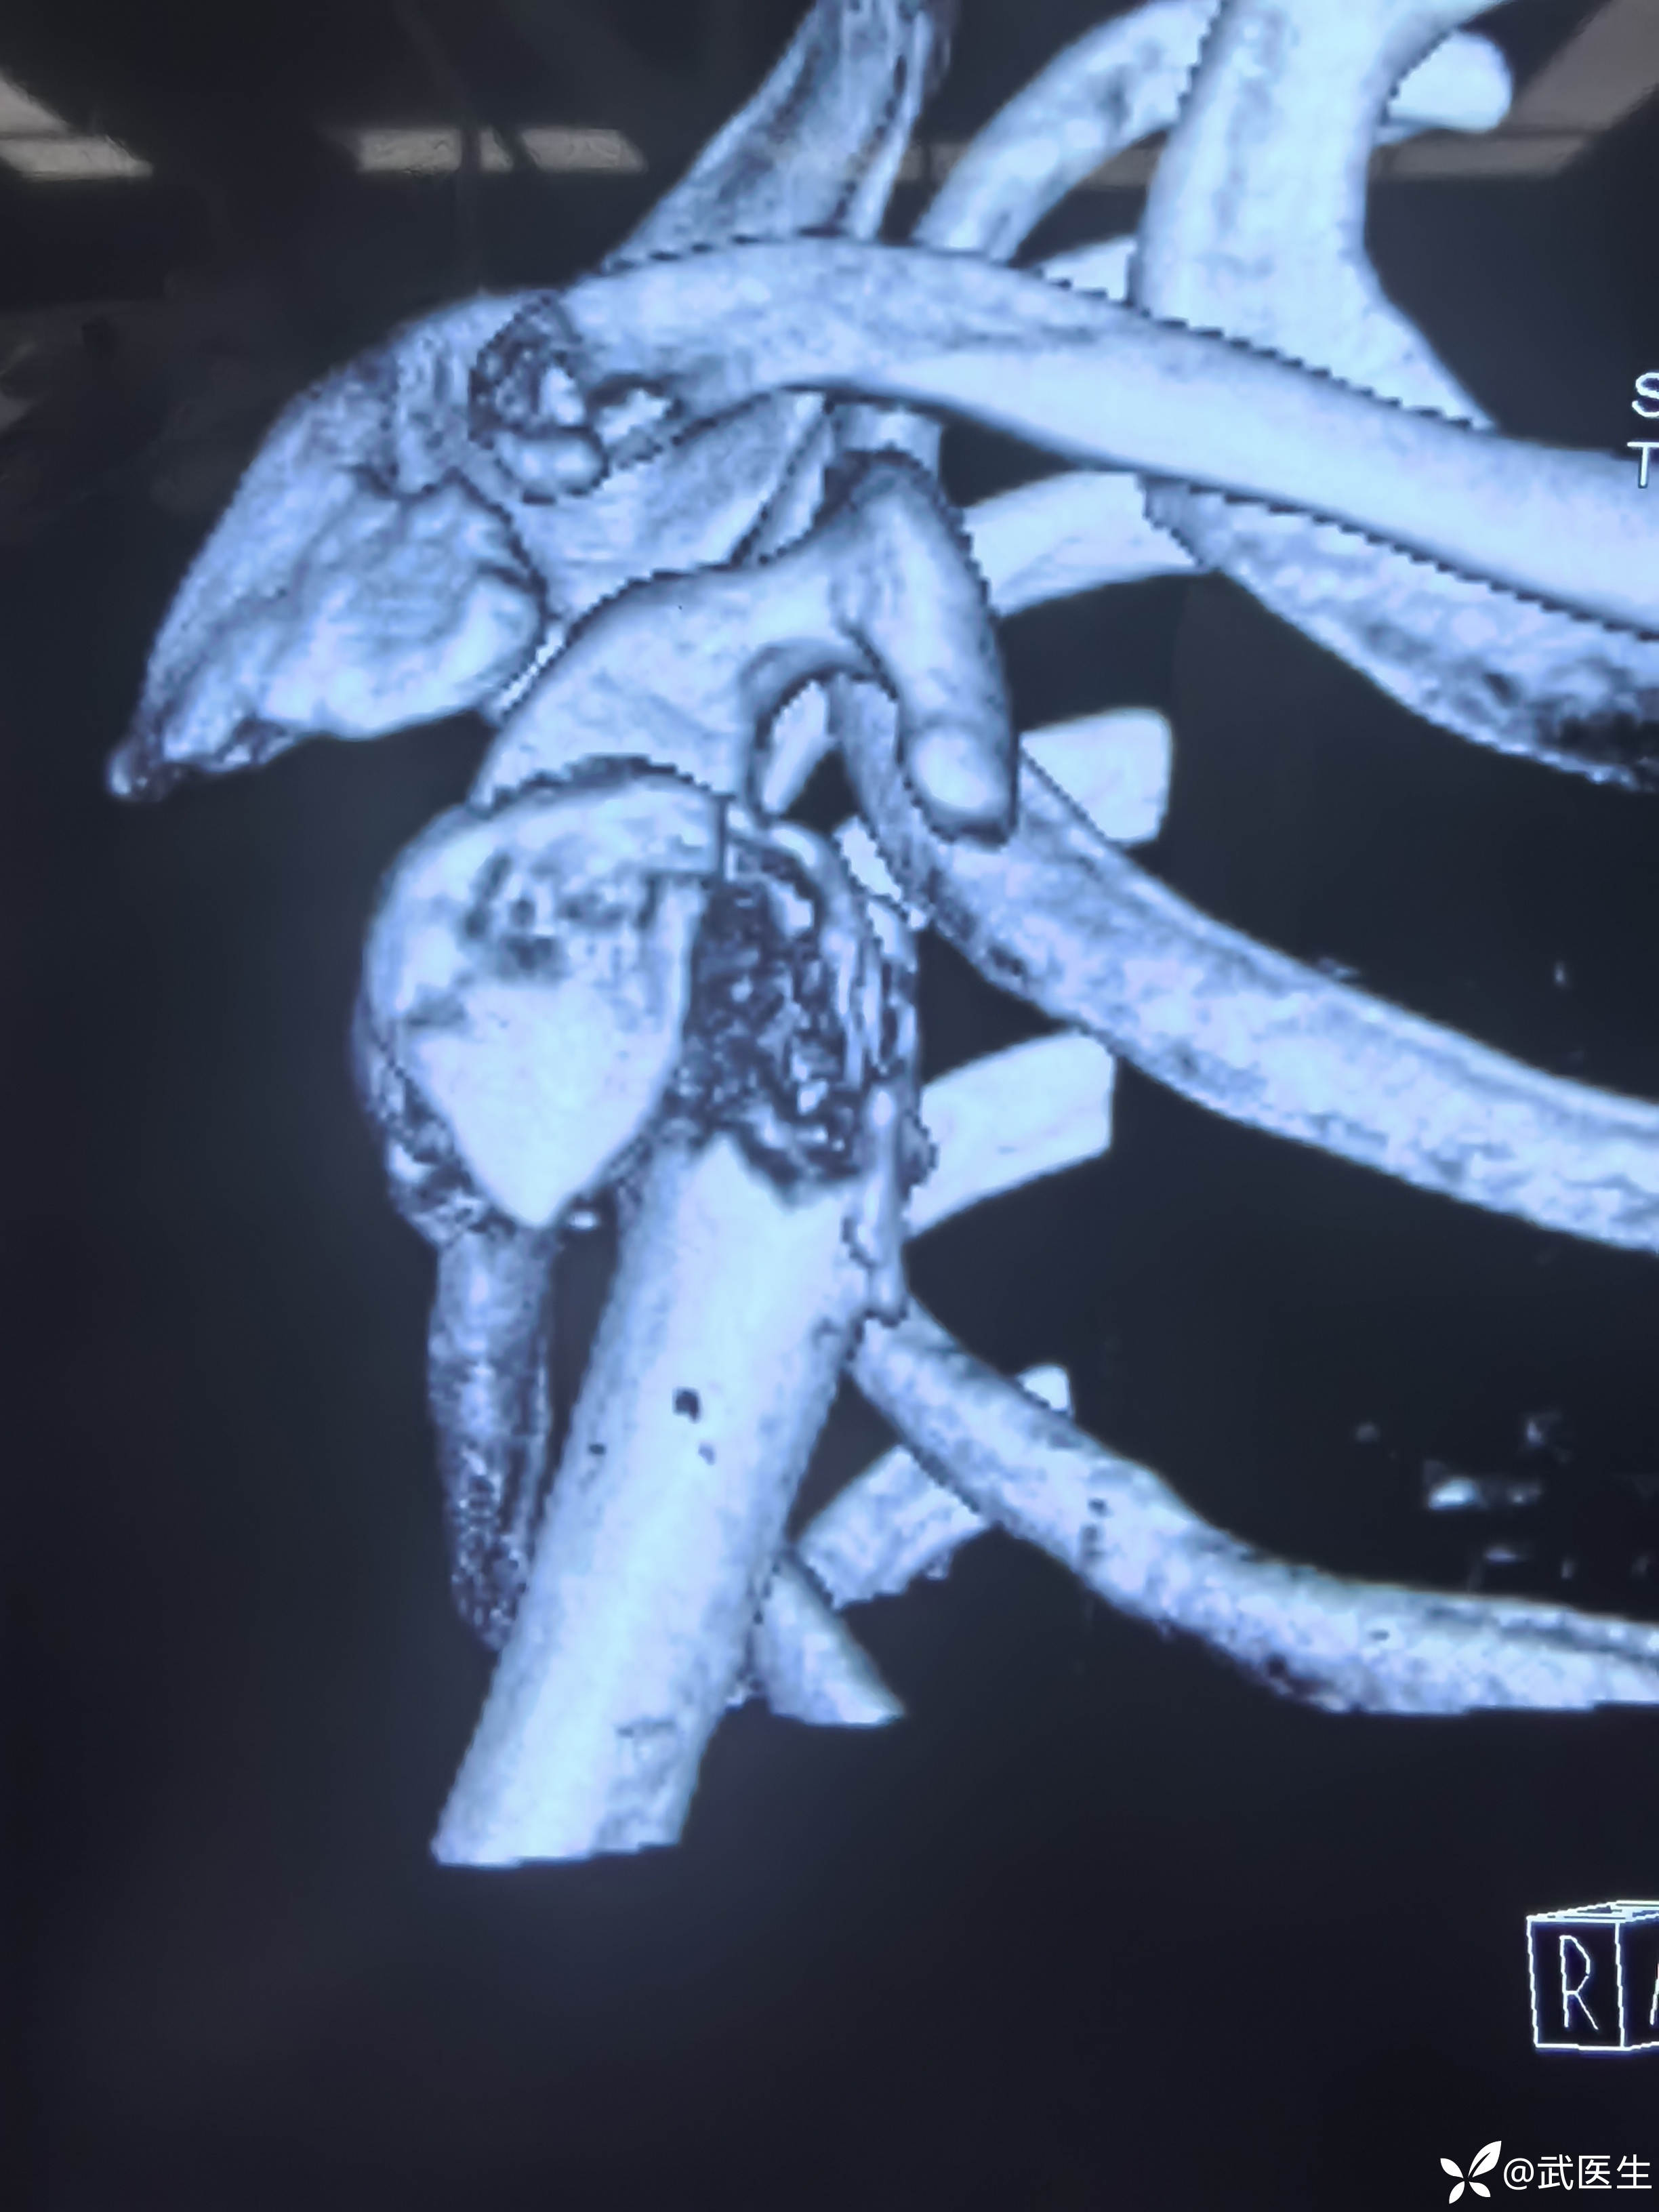

汇报一例肱骨近端四部分骨折脱位

【临床诊断】:右肱骨外科颈四部分骨折脱位,左桡骨远端骨折伴桡腕关节半脱位。钩骨骨折。头面部软组织损伤。

【治疗经过及结果】:入院完善检查,择期安排手术。患者年轻,肱骨外科颈骨折选择保头治疗。择期安排。